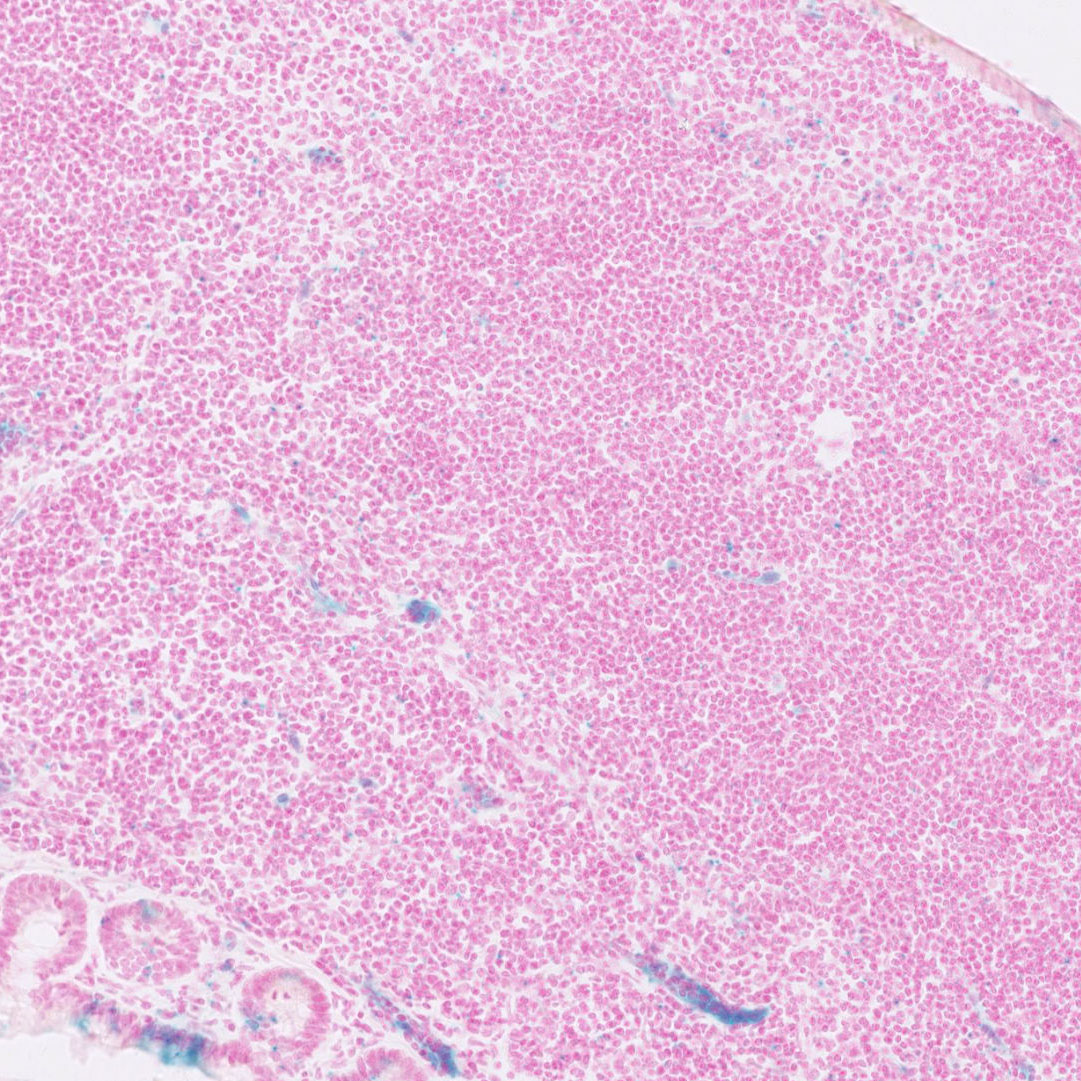

Images

Drag images to compare to others or to data in the table below. Drag corners to resize images for more detail.

Recombinase Activity